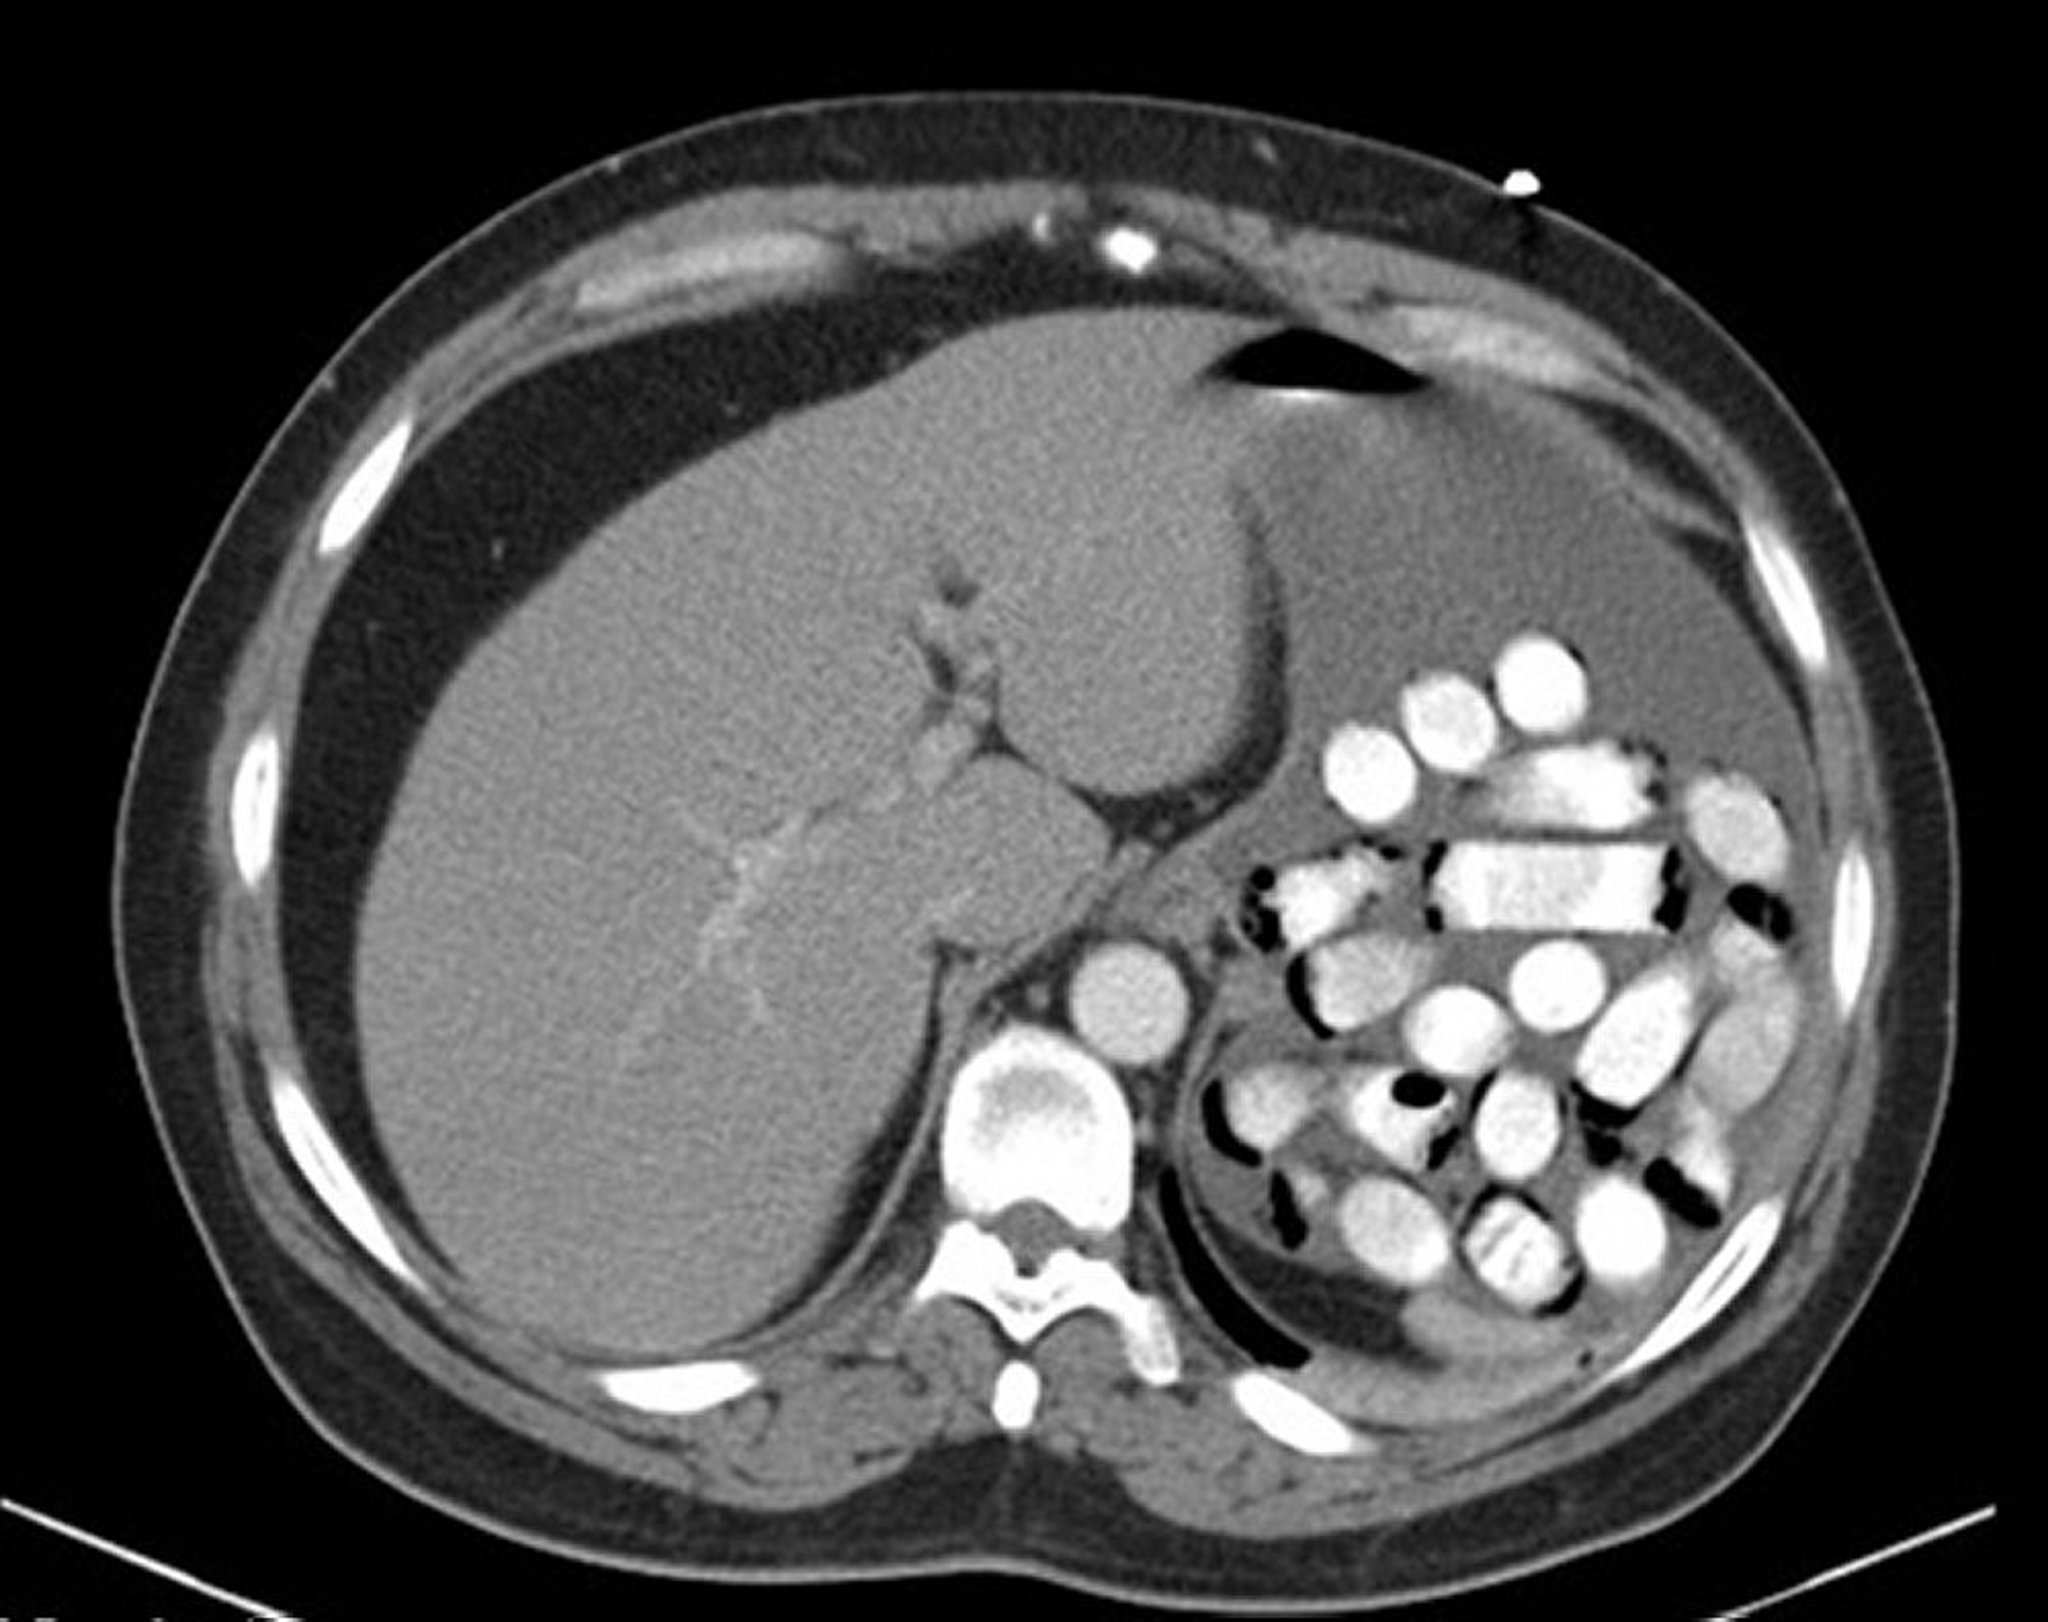

Corpo estraneo gastrico (TC)

Questa immagine mostra pacchetti di droga nello stomaco.

Immagine fornita da Alan Gingold, DO.